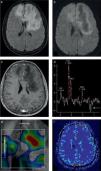

En los últimos años, se ha destacado la importancia de utilizar esta secuencia con pulsos de saturación grasa y luego de administrar el medio de contraste: mientras la primera aumenta el contraste entre la sustancia gris y blanca, con una mejora consiguiente de la resolución; la poscontraste tiene una mayor sensibilidad en la detección de alteraciones meníngeas, tanto de colecciones líquidas (sobre todo empiemas subdurales) como del compromiso leptomeníngeo observado en las meningitis de distinta etiología8–10 (fig. 1).

Paciente con meningitis tuberculosa confirmada. Se muestra la utilidad y los hallazgos de la secuencia FLAIR luego de administrar el contraste. (a, b y c) En los cortes axiales se identifica el intenso realce y la ocupación de la cisterna de Silvio del lado derecho por el depósito de material granulomatoso (característico de esta patología). (d, e y f) Mismo paciente: en los cortes sagital y axial de la secuencia SE ponderada en T1 con contraste se observan los hallazgos ya identificados claramente en la secuencia anterior.

Algunos autores sugieren que la sensibilidad de las secuencias FLAIR posgadolinio y las ponderadas en T1 es idéntica en el diagnóstico de la patología infecciosa leptomeníngea, pero que la FLAIR tiene mayor especificidad10. Incluso, otras comunicaciones, como la de Splendiani et al.11, demuestran la utilidad de la RM con secuencias FLAIR poscontraste en el diagnóstico precoz de casos con meningitis infecciosa. No obstante, a pesar de estos estudios y de que nuestra experiencia sea muy similar en un número significativo de pacientes, es necesario destacar que las secuencias convencionales ponderadas en T1 con contraste no son sustituibles en esta población.